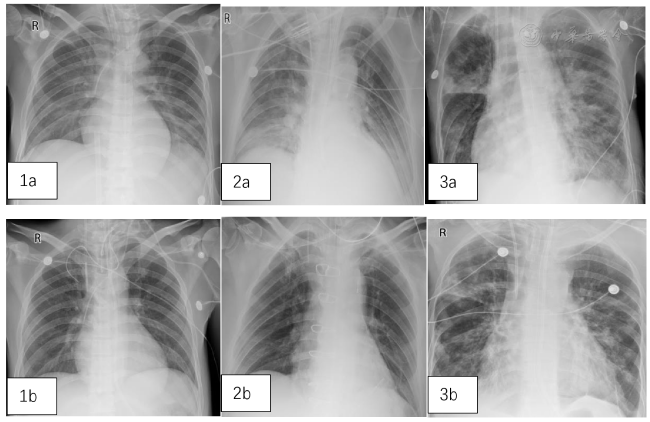

图1 3例患者治疗前后肺部影像学对比。图1a、2a、3a分别为病例1、2、3治疗前,图1b、2b、3b分别为病例1、2、3治疗2周后